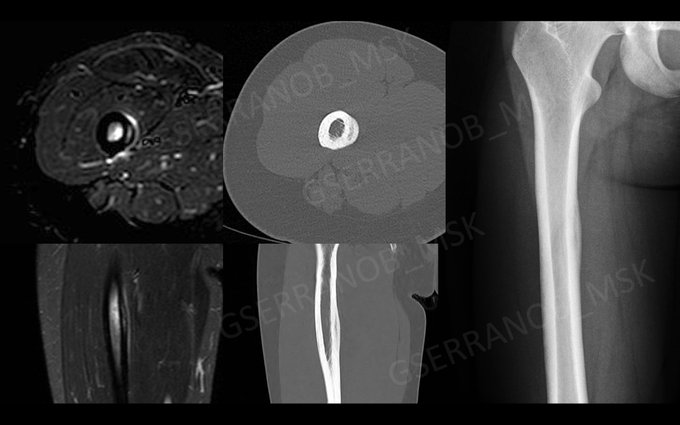

I think your first description is just fine 👍. 4a or 4b, The kid needs to calm down. A companion case with Rx, CT and MRI.